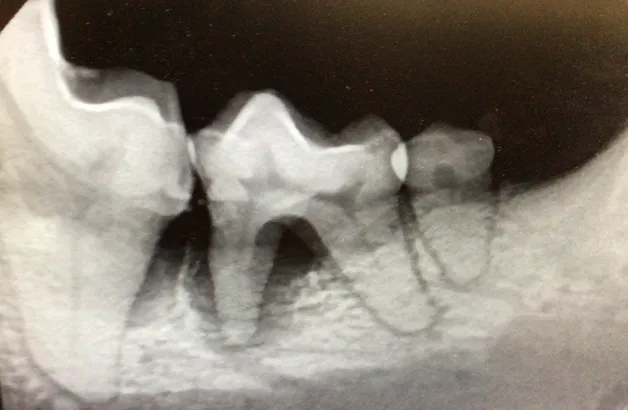

dental rads

• Digital dental radiography